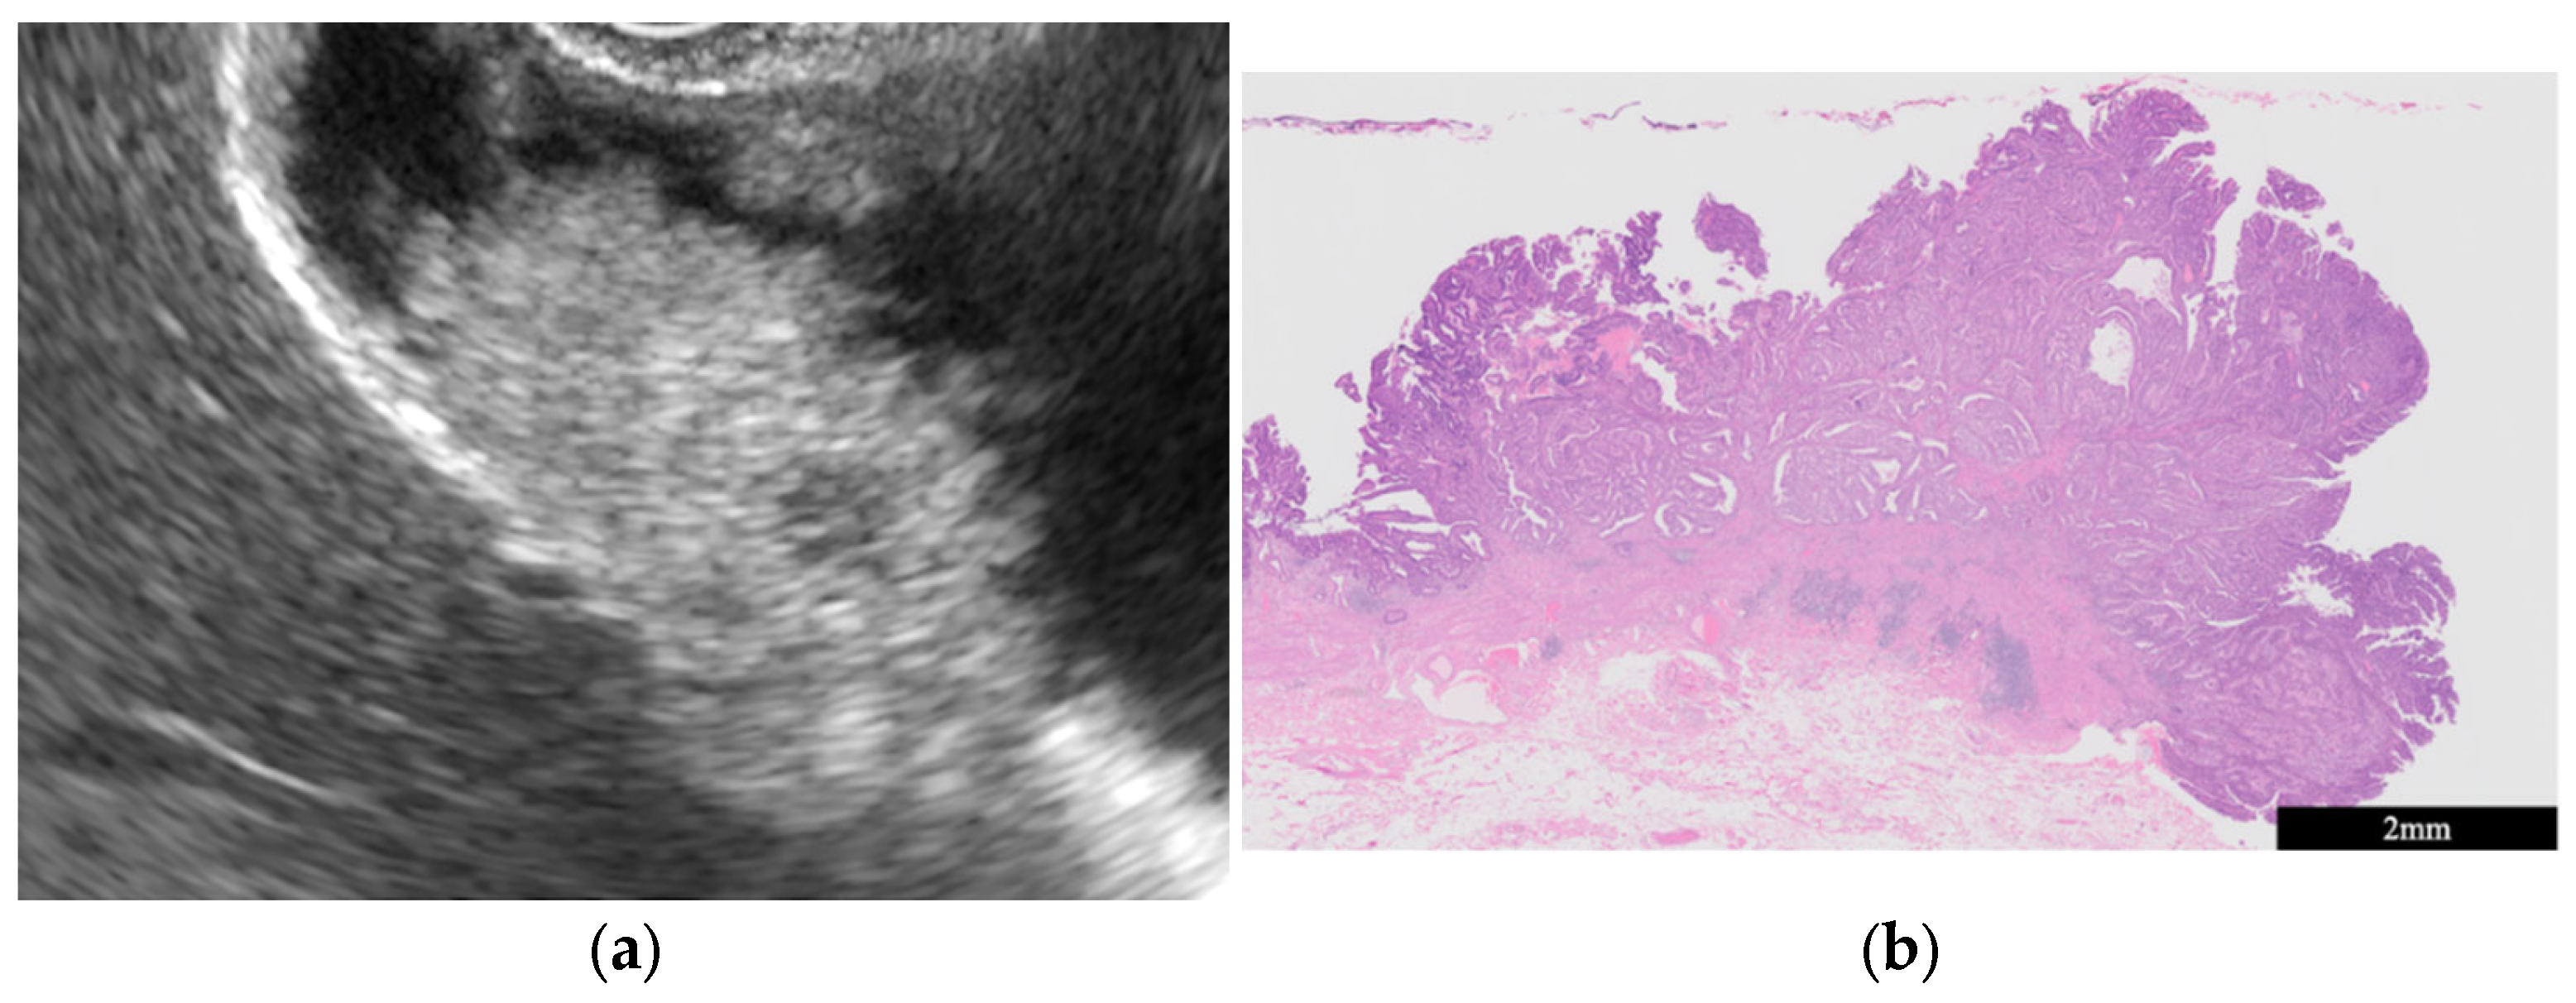

- GB mucosal hyperplasia associated with pancreaticobiliary maljunction (PBM) (Figure 4)

| GB mucosal hyperplasia associated with pancreaticobiliary maljunction | Smooth | Uniform hypoechogenicity | Preserved |